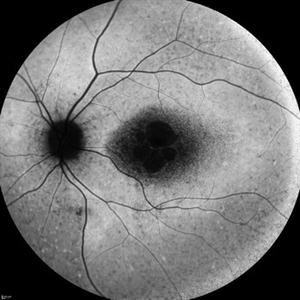

Central Serous Chorioretinopathy

Apr 15 2025 by Filip Kecer

FA&ICG late phase of a young woman with CSCR

Photographer: Filip Kecer, Oftalmocentrum Betliarska, Bratislava, Slovakia

Imaging device: Spectralis, Heidelberg Engineering

Condition/keywords: central serous chorioretinopathy (CSCR), Central Serous Chorioretinopathy (CSR), FA late phase, indocyanine green (ICG) angiography